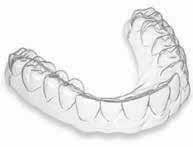

A bench scan (Medit T-710 Tabletop Scanner) of the cast and preoperative CBCT (3D Accuitomo 170) was made for each participant for the construction of a CAD CAM surgical guide. The implant was planned to engage the palatal wall, avoid pressure on the labial plate of the bone, and be 1-mm apical to the crest. A fully guided tooth-supported surgical guide was designed and then printed in clear acrylic resin (Dental SG Resin; Formlabs) by using a 3D printer (Form2; Formlabs). (fig 2)